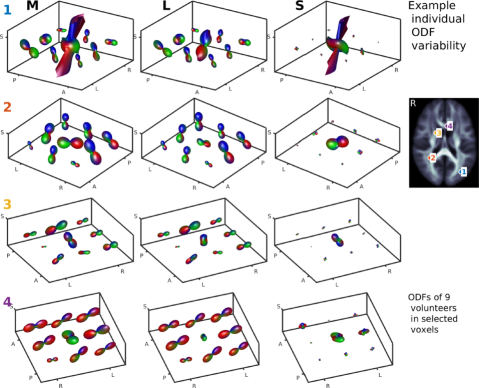

The ODFs in each voxel of a set of registered whole brain diffusion datasets can be expected to be highly correlated within that voxel (Fig. 1). Although subject subgroup differences can arise, one can assume that all ODFs will be drawn from a lower-dimensional subspace. This means that the ODF features which are common between or within subject groups will be captured in that low-dimensional subspace if we, for a moment, ignore the sparse individual variability. The low-dimension assumption of the ODFs can be translated in an assumption of low rank (Zhou et al., 2014; Lin, 2016) where the rank of a matrix is the number of linearly independent rows or columns that define a basis set to represent the matrix. Hence, once we identify the low-rank subspace of the ODFs, we can easily identify the ODF features different between subject subgroups.

The individual variability of ODFs can be caused by ODF reconstruction errors due to image artifacts (Fig. S5.1), registration errors and individual differences in brain structure (Fig. S5.3-4). In the HCP ODFs individual variability due to the first two of these contributions is limited by the low number of artifacts and the high image resolution in the HCP DWI images. As a result, ODF correlations of BMI identified with ODF ((Fig. 9g,h, S3c,d)) and ODF (Fig. 9i,j, 7) are similar in this dataset. However, in a dataset with higher individual variation, notable improvement of ODF over ODF PCA can be observed (Baete et al., 2016a).